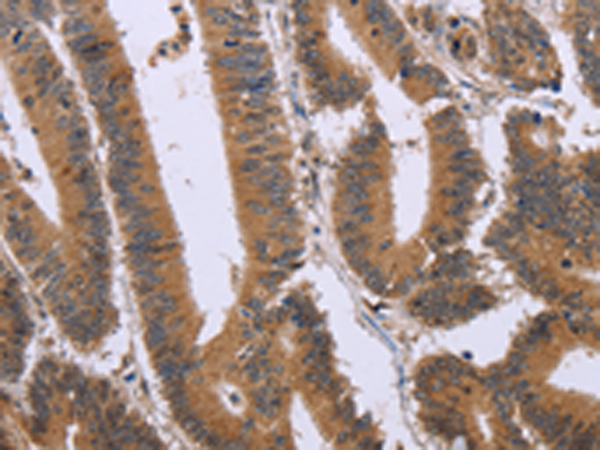

分类: 科研抗体货号: P08304别名: D5D; TU12; FADS6; FADSD5; LLCDL1应用: WB,IHC反应种属: Human, Mouse, Rat